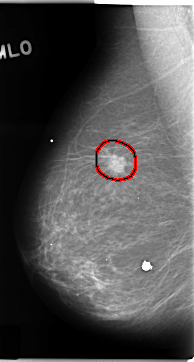

C_0156_1.RIGHT_CC

FILE: C_0156_1.RIGHT_CC.OVERLAY

TOTAL_ABNORMALITIES 1

ABNORMALITY 1

LESION_TYPE MASS SHAPE IRREGULAR MARGINS SPICULATED

ASSESSMENT 5

SUBTLETY 5

PATHOLOGY MALIGNANT

TOTAL_OUTLINES 1

BOUNDARY